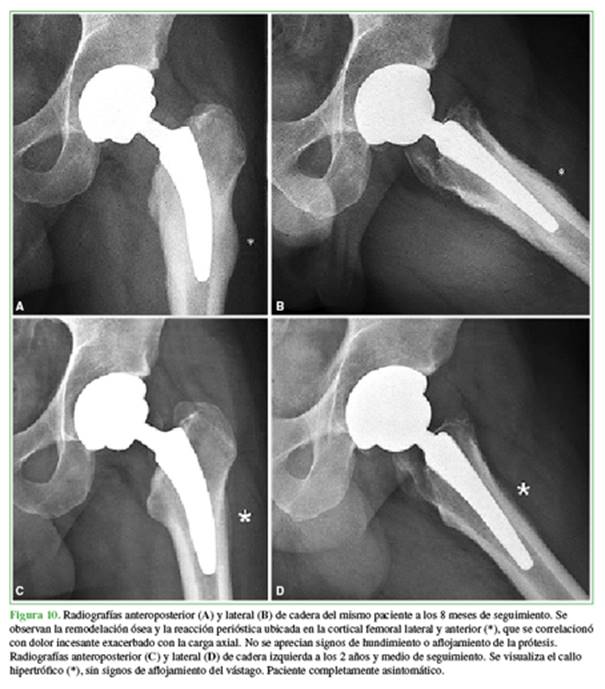

La ATC con una prótesis de vástago corto ya ha demostrado excelentes resultados clínicos y radiológicos a mediano y largo plazo61,62 resultados variables de supervivencia entre el 92,2% y el 100%.63-66 Sin embargo, no todos los diseños son similares en tamaño y forma;13 por lo tanto, distintas distribuciones de carga hacia el fémur proximal pueden desencadenar diferentes patrones de remodelación ósea, generando diferentes resultados clínicos y radiológicos.13,33 Cuando se diagnostica dolor de muslo posoperatorio, entender sus etiologías potenciales es fundamental para seleccionar la modalidad de tratamiento adecuada. Originalmente, se intentó disminuir la rigidez estructural con diseños modernos de vástagos no cementados;67 sin embargo, la transferencia de tensión excesiva derivada de un desajuste en la rigidez a la flexión ha sido una preocupación en términos de alteraciones mecánicas en el módulo de elasticidad del fémur proximal, y la generación de dolor es una consecuencia potencial.67,68 Con el advenimiento de los vástagos cortos, muchas investigaciones han centrado su atención en el dolor de muslo y han aparecido muchas teorías más recientes para explicar su génesis.13,33 En algunas situaciones, las radiografías posoperatorias pueden mostrar hipertrofia cortical como consecuencia de la remodelación ósea que casi siempre es un evento asintomático. Maier y cols. han analizado los resultados clínicos y radiológicos de sus primeras 100 ATC consecutivas con el vástago Fitmore® (Zimmer, Warsaw, IN, EE.UU.).69 Tras un seguimiento medio de 3.3 años (rango 2-4.4), la supervivencia fue del 100% tomando la revisión por cualquier motivo como falla, sin reportar aflojamiento del componente femoral. Sin embargo, se observó una hipertrofia cortical en 50 caderas, predominantemente en las zonas 3 y 5 de Gruen.47,69 De ellos, dos pacientes refirieron dolor moderado en el muslo que se agudizó durante el ejercicio físico. Dicho esto, en la Argentina, se ha reportado un caso de fractura por estrés inusual en un hombre de 43 años de edad, golfista profesional, en la punta distal lateral de un vástago corto no cementado con fijación metafisaria70 (Figura 10).

Después de descartar infección y aflojamiento, los autores sugieren a los cirujanos reconstructivos ser conscientes de la existencia de fracturas periprotésicas por estrés como fuente de dolor en el muslo (a veces insospechada) y, a pesar de ser poco frecuentes, siempre deben contemplarse, debido a que estos casos pueden ser manejados de forma conservadora con reposo y descarga parcial. Se sugiere, como ya se mencionó, alinear el vástago sutilmente en varo para distribuir las cargas de igual forma en el calcar medial y la cortical femoral lateral.42,71